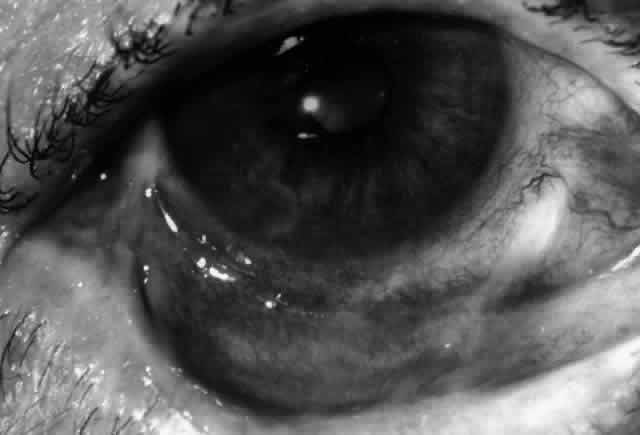

Ocular Manifestations

Clinically, the ocular disease in cicatricial pemphigoid (OCP) may present unilaterally in the form of a chronic, recurrent catarrhal conjunctivitis, but it eventually becomes bilateral. Subepithelial fibrosis is characteristic of stage 1 of OCP (Fig. 7). Stage 2 shows fornix foreshortening (Fig. 8), and symblepharon formation is the hallmark of stage 3 (Fig. 9). Stage 4, end-stage disease, is characterized by ankyloblepharon and surface keratinization (Fig. 10). Obstruction of the lacrimal ductules and meibomian gland ducts eventually produces an unstable tear film and progressive sicca syndrome, but it is to be emphasized that OCP is not a dry-eye syndrome until late in the disease course.20 Trichiasis and entropion occur because of the subepithelial fibrosis, with eventual keratopathy, corneal neovascularization, and corneal ulceration and scarring.20

Fig. 7. Stage 1 cicatricial pemphigoid, with cicatrizing conjunctivitis, and fine striae-type areas of subepithelial fibrosis, but without evidence of shrinkage of the conjunctiva.